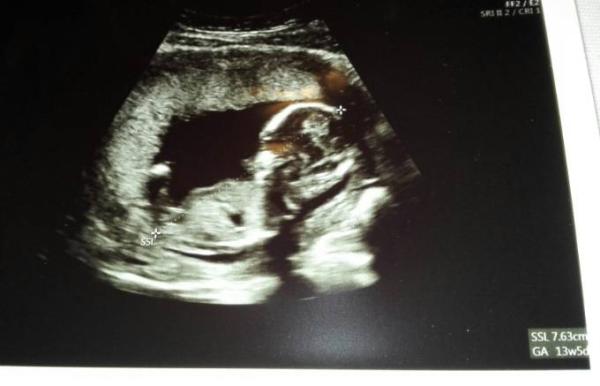

Bei der Ärztin meinte ich dann, dass der errechnete Termin im Mutterpass falsch wäre (da stand 6.6. - warum auch immer). Ich meinte, dass es nach meiner Rechnung der 11.7. wäre. Im Computer stand 15.7. (das war noch vom ersten Ultraschall in der 7. SSW). Trotz der letzten Messung und dieser, die beide die Größe ergaben, die genau zum 11.7. passen, wurde der ET nur auf den 15.7. korrigiert. Jetzt steht im Mutterpass immer, was die SSL ergeben hat unter Bemerkungen und vorne die Woche, die ich falsch sehe. An sich ist das nicht tragisch, aber so beginnt mein Mutterschutz ein paar Tage später. Wie ist das eigentlich? Bekomm ich, wenn das Kind vor dem 15.7. kommt, dann die Tage hinten ran gutgeschrieben?

Mein Würmli ist etwa 7,6 cm klein und lag wirklich auch so, wie ich es heute gespürt hatte. Ich konnte sagen, wo die Füßchen sind.